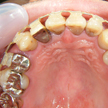

2. 初診時上顎面観

全顎パノラマ写真においては右上1番が失活歯、2番は叢生のままで不適合な前装冠(差し歯)、八重歯の3番は健全歯、4,5番も2番同様不適合冠処置となっています。比較的プラークコントロール(以下PCR)の良好な(歯ブラシの仕方が上手な)この患者様も同部が上手に磨けず不潔となり崩壊過程にあることが考えられます。

3. 初診時上顎

上顎面観では正面観よりも八重歯が顕著です。この部位2,3,4番はPCR良好な方でもまともには清掃できません。この八重歯でよく口唇に咬傷を作るうえ、ご自身でも上手く磨けずせっかくセラミックを入れたのに臭いがすると訴えておられます。4番にはパーシャルバイクのセラミック冠(自費診療と思われる)が入っています。結果論ですがこの4番の崩壊が一番顕著で抜歯となってしまいました。患者様には「高額の費用だったのに一番先にダメになった」と医療不信を持たれる原因となりました。